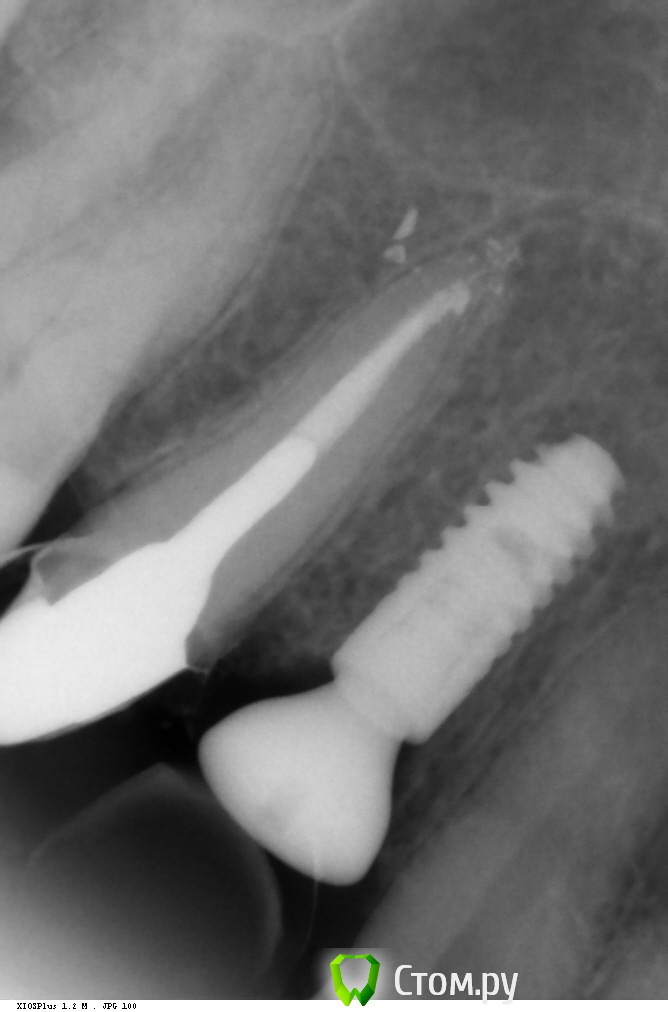

Фит на 15.

14 - одномоментно с удалением. медиально кость ушла? будут проблемы или нет? Дмитрий запугал вконец )